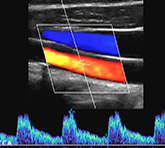

Dr. Shah is a well respected vascular surgeon in Manhattan, Brooklyn and Staten Island. His practice provides management and treatment for peripheral arterial disease, stroke prevention, AAA repair, dialysis care, venous disorders and varicose veins. We have earned our unrivaled reputation by providing premier vascular care. Please visit us and see why.